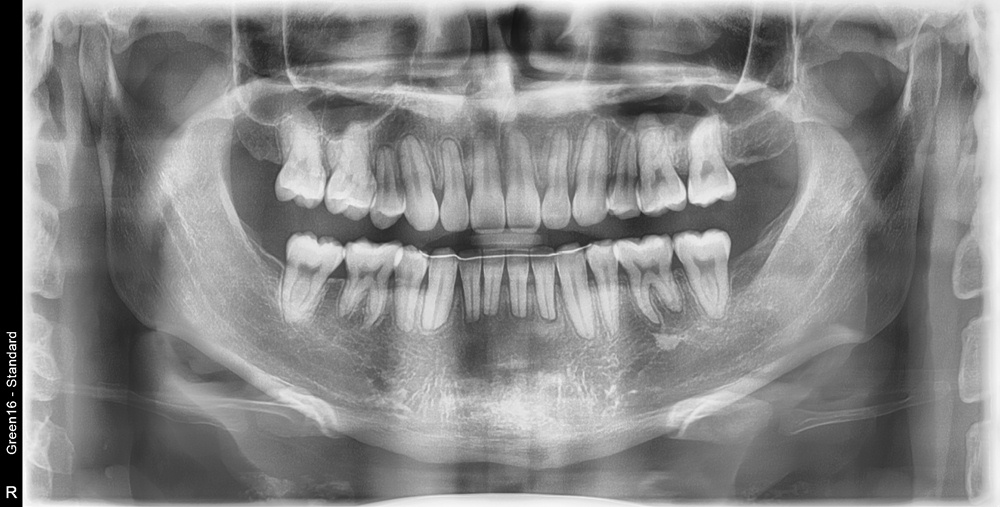

치료 후 사진입니다.